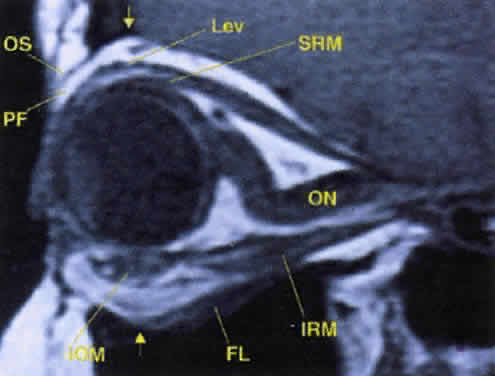

Fig. 17. The optic nerve (ON). A parasagittal MR image demonstrates the 7-mm excess of intraorbital optic nerve, seen as an S shape. Also note the perpendicular relation of the inferior oblique muscle (IOM) to the inferior rectus muscle (IRM). Other findings of anatomic interest in this image include the levator (Lev), the superior rectus muscle (SRM), the orbital septum (OS) arising from the arcus marginalis, and the preaponeurotic fat pad (PF) between the septum and the levator. Note that the orbital floor (FL) is angled upward by 15° to 20° from anterior to posterior.

Tables 10 and 11 summarize the important features of each of the cranial nerves supplying the orbit (Fig. 16, see Fig. 12). Several points are worth mentioning. First, the optic nerve assumes an S-shaped course within the orbit. Because the intraorbital nerve is about 25 mm long and the distance from the back of the globe to the optic foramen is 18 mm, 7 mm of slack remains. This degree of potential mobility allows the nerve to remain unaffected during ocular rotations and provides a cushion for axial proptosis (Fig. 17).

As the levator palpebrae superioris (levator) muscle and superior rectus muscle course anteriorly, diffuse connections form to the orbital roof, creating an effective suspensory system. Further, diffuse fascial connections form between the levator and superior rectus muscles, allowing precise coordination of upper eyelid retraction with upgaze. Note that on imaging studies, the close association of these two muscles often makes them look like a single anatomic unit; the term “levator-superior rectus complex”is often found in radiologic reports (see Fig. 17). A fascial sling forms beneath the superior rectus muscle to provide suspensory support for the superior ophthalmic vein.